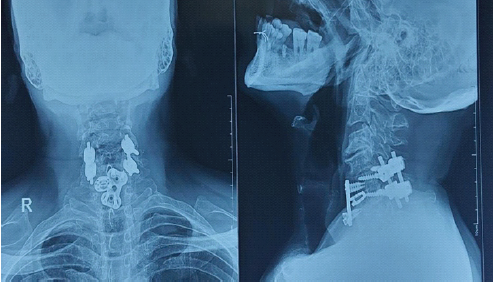

Post-operative neurological evaluation demonstrated significant improvement, particularly in motor function. Upper-limb motor strength improved to 4/5 on the right side from C5 to T1, and on the left side, it improved to 3/5 till C7, with residual weakness at C8 on the left side. Lower-limb motor power improved to 5/5 bilaterally from L2 to S1. Sensory examination showed improvement in upper-limb sensation. Lower-limb and sacral sensations remained intact. Reflexes and muscle tone remained normal. The patient continued to demonstrate neurological recovery with upper-limb motor strength improving to 5/5 on the right side from C5 to T1, and on the left side, it improved to 4/5 till C7, with residual weakness at C8, more pronounced on the left side at the end of 3 months. At 2-year follow-up, lower-limb motor power was maintained at 5/5 bilaterally from L2 to S1, enabling functional ambulation, with a marked reduction in the upper-limb motor deficit, consistent with expected recovery patterns in CCS. At 2-year follow-up, the radiograph showed intact implants with mild screw loosening (Fig. 8), and left side upper-limb power had improved, with no residual defects (Fig. 9).

Figure 8: Post-operative cervical spine radiograph showing anterior-posterior and lateral views at 2-year follow-up.